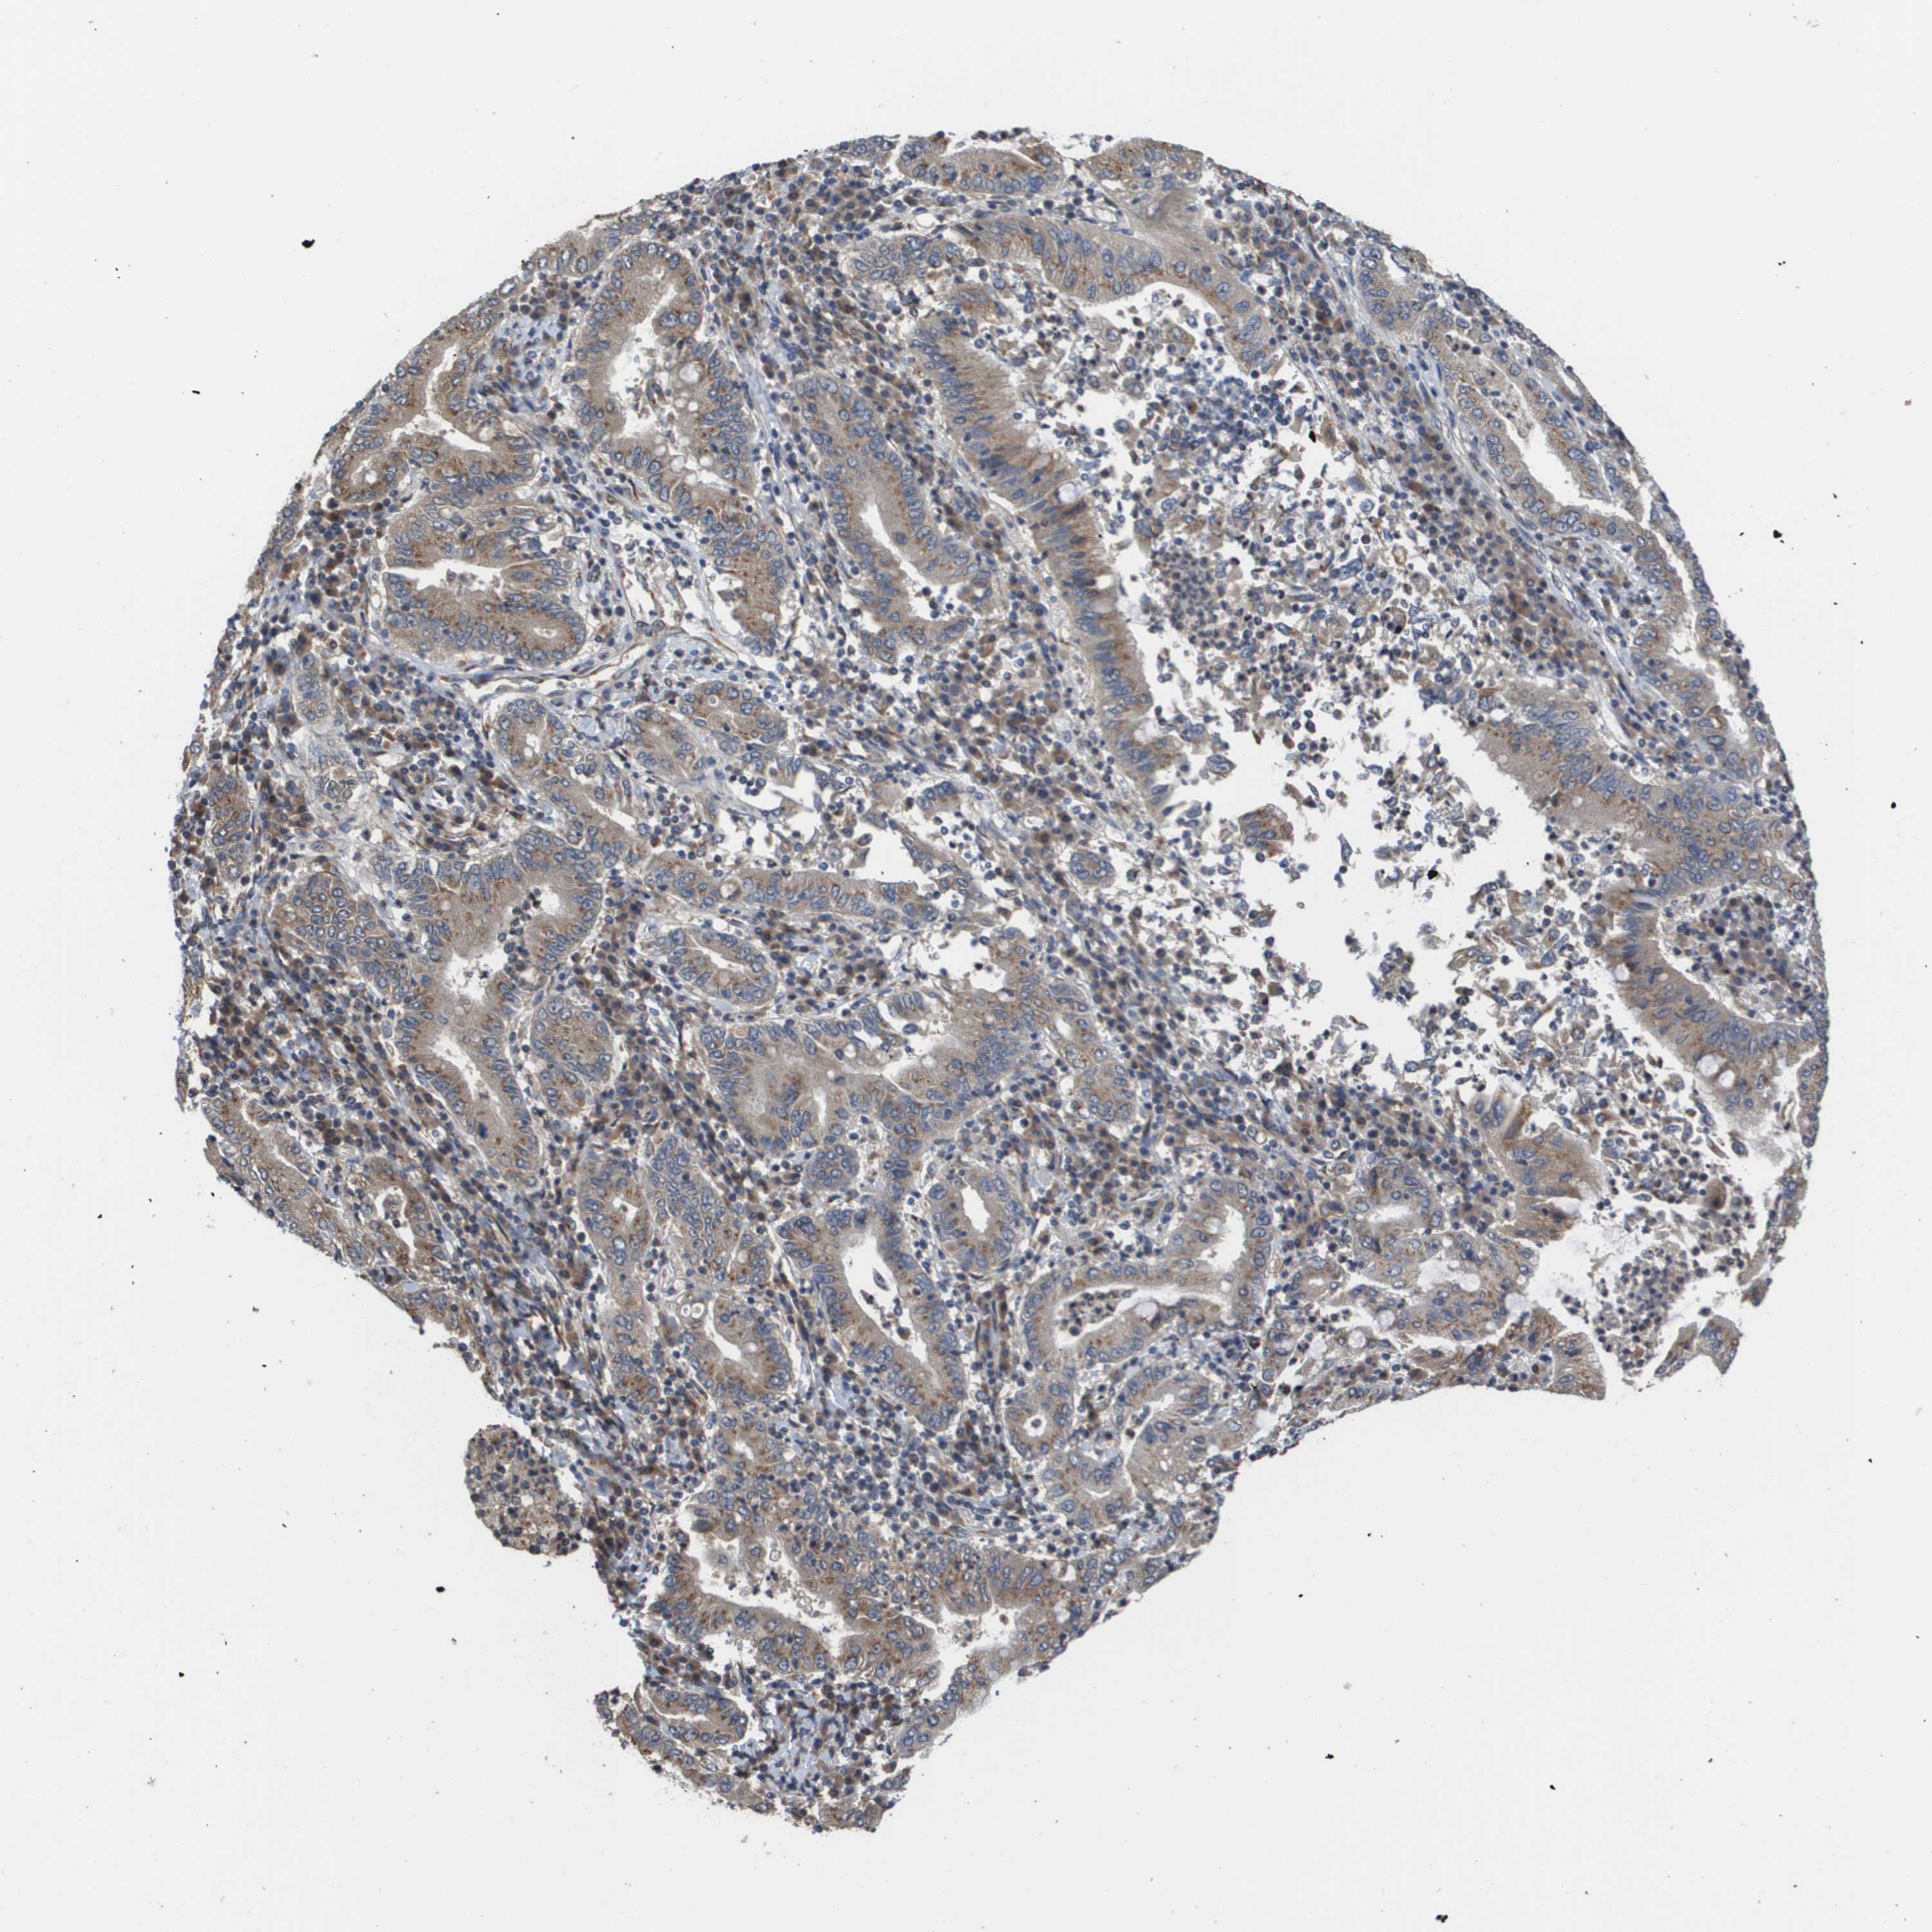

STOMACH CANCER - Protein expressioni

A mouse-over function shows sample information and annotation data. Click on an image to view it in a full screen mode. Samples can be filtered based on level of antibody staining by selecting one or several of the following categories: high, medium, low and not detected. The assay and annotation is described here.

Note that samples used for immunohistochemistry by the Human Protein Atlas do not correspond to samples in the TCGA dataset.

Antibody stainingi

Antibody staining in the annotated cell types in the current human tissue is reported as not detected, low, medium, or high, based on conventional immunohistochemistry profiling in selected tissues. This score is based on the combination of the staining intensity and fraction of stained cells.

Each image is clickable and will lead to virtual microscopy that enables deeper exploration of all samples and also displays staining intensity scores, fraction scores and subcellular localization as well as patient and tissue information for each sample.

Antibody HPA006277

Antibody HPA006507

Antibody CAB017027

Staining

High

Medium

Low

Not detected

Intensity

Strong

Moderate

Weak

Negative

Quantity

>75%

75%-25%

<25%

None

Location

Nuclear

Cytoplasmic/membranous

Cytoplasmic/membranous,nuclear

Adenocarcinoma, NOS

Adenocarcinoma, High grade